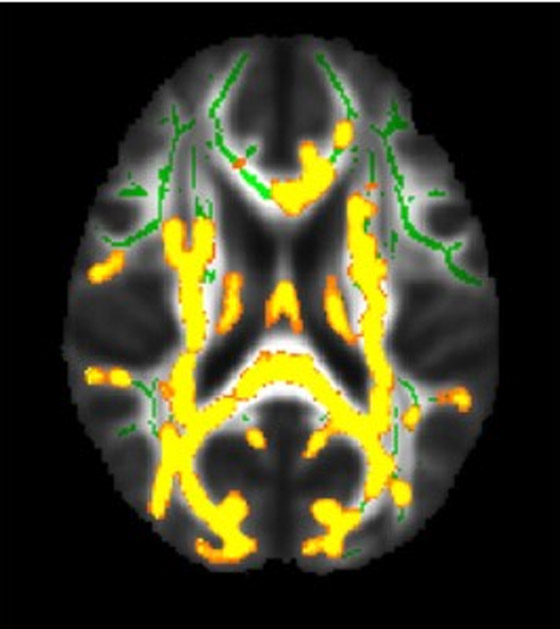

إلى ذلك ولإلقاء نظرة فاحصة على التأثير المحتمل للدهون الحشوية على خطر الإصابة بمرض الزهايمر، قام راجي وزملاؤه بتحليل بيانات من 54 متطوعاً تتراوح أعمارهم بين 40 إلى 60 عاماً وكان متوسط مؤشر كتلة الجسم لديهم 32،  وقام الباحثون بقياس مجموعة من المعايير الصحية، بما في ذلك مستويات الأنسولين والسكر في الدم. وباستخدام فحوصات التصوير بالرنين المغناطيسي، قاموا بتقييم كمية الدهون الموجودة تحت الجلد مباشرة كذلك ما كان يحيط بالأعضاء. كذلك تم استخدام التصوير بالرنين المغناطيسي أيضاً لقياس سمك الطبقة الخارجية للدماغ المسؤولة عن وظائف مثل الكلام والإدراك والذاكرة طويلة المدى والحكم، والتي تصبح أرق مع تقدم مرض الزهايمر.

ووجد الباحثون أن المشاركين الذين لديهم المزيد من الدهون الحشوية لديهم تراكمات أكبر من الأميلويد في أدمغتهم، مما يشير إلى أنهم قد يكونون أكثر عرضة للإصابة بمرض الزهايمر. في حين أكد راجي إن الأبحاث السابقة أظهرت أن الالتهاب وارتفاع مستويات الأنسولين، والتي يمكن أن تمنع البروتينات التي تكسر الأميلويد في الدماغ، ترتبط بالدهون الحشوية. ولأن التطور المبكر لمرض الزهايمر في الدماغ يمكن أن يبدأ قبل 20 عاماً من ظهور الأعراض الأولى، يخطط الباحثون لدراسة التأثير المحتمل طويل المدى للدهون الحشوية من خلال متابعة المشاركين في الدراسة.